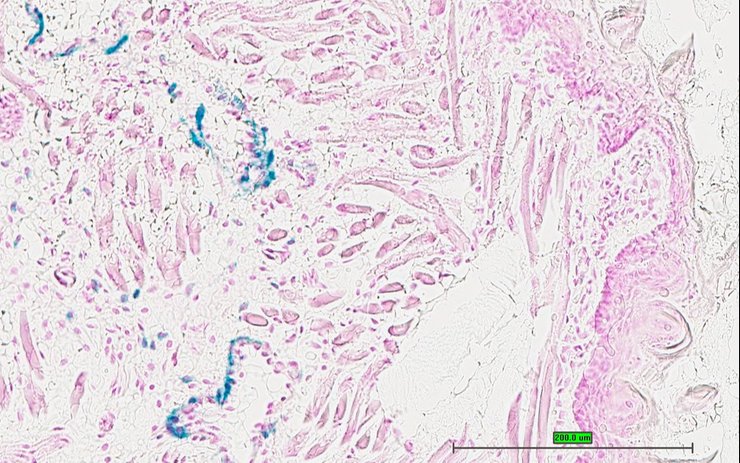

Specimen UC Davis_1877881: postnatal adult; Taf9btm1.1(KOMP)Vlcg/Y (more )

Structure Level Pattern Image Note

TS28: stomach Present UC Davis_1877881